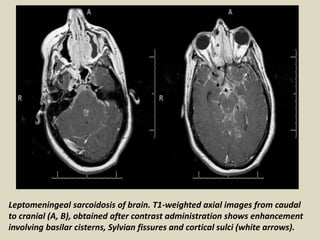

Leptomeningeal sarcoidosis of brain. T1-weighted axial images from caudal

to cranial (A, B), obtained after contrast administration shows enhancement

involving basilar cisterns, Sylvian fissures and cortical sulci (white arrows).